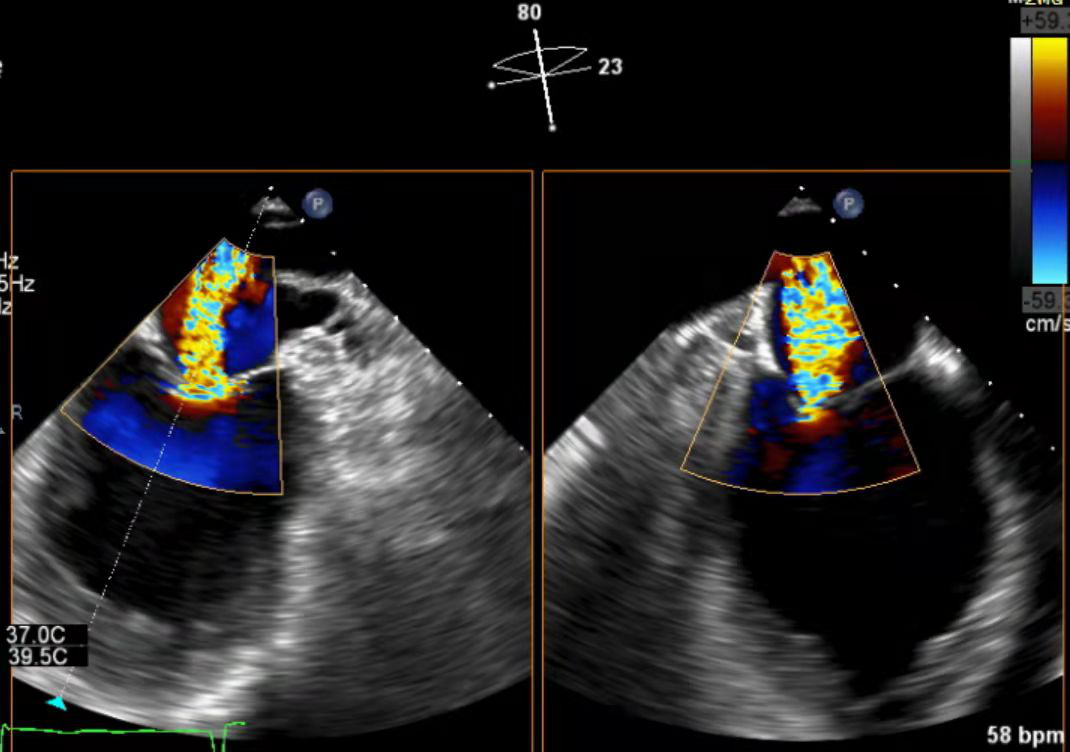

手术在患者全麻状态下进行,经股静脉入路,穿刺房间隔后在经食道超声和DSA引导下将瓣膜夹器械输送到左心室,采取单独捕捉策略,先后钳夹二尖瓣前叶和后叶并关闭瓣膜夹,经食道超声反复确认手术效果后,最终释放0609型瓣膜夹,患者术后平均跨瓣压差3mmHg,患者即刻二尖瓣轻度反流,术后第二天自觉临床症状改善明显。

术后心超